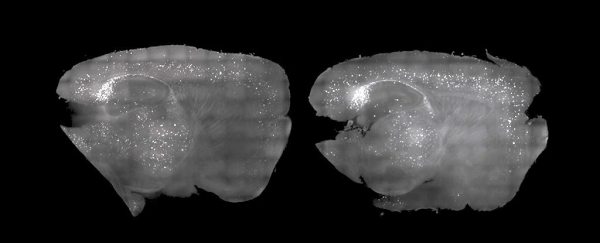

Исследователи показали, что стробоскопы и слабый гул могут использоваться для генерации мозговых волн — гамма-ритма, который ухудшается при нейродегенеративном заболевании. В ходе эксперимента новый метод позволил снизить число скоплений патогенных белков и улучшить когнитивные функции у мышей, страдающих от состояния, аналогичного болезни Альцгеймера у людей.

Визуальная стимуляция выражалась в мигании света 40 раз в секунду, а слуховая — в воздействии звука с той же частотой, то есть 40 Гц. При этом наблюдались изменения в гиппокампе и префронтальной коре головного мозга грызунов и уменьшение бляшек, образованных тау-белками и амилоидами. Считается, что эти соединения играют одну из ключевых ролей в нейродегенеративных процессах.